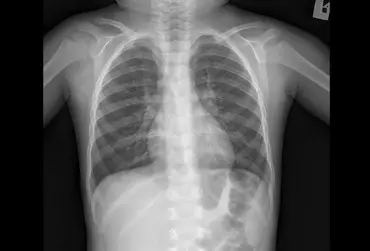

Duszność, tachypnoe, słaby przyrost masy ciała to objawy spotykane w przebiegu różnych schorzeń u dzieci. Celem niniejszej pracy jest zwrócenie uwagi na rzadkie przyczyny występowania wyżej wymienionych objawów, takie jak choroby śródmiąższowe płuc. W artykule przedstawiono dwa przypadki niemowląt, u których rozpoznano neuroendokrynną hiperplazję płuc wieku niemowlęcego (dawniej przetrwałe tachypnoe niemowląt), jedną z chorób śródmiąższowych o dobrym rokowaniu. Podstawę rozpoznania stanowiły charakterystyczny przebieg kliniczny oraz obraz radiologiczny (HRCT klatki piersiowej). W artykule zwrócono szczególną uwagę na diagnostykę różnicową stanów przebiegających z dusznością oraz przybliżono patofizjologię opisywanego schorzenia.